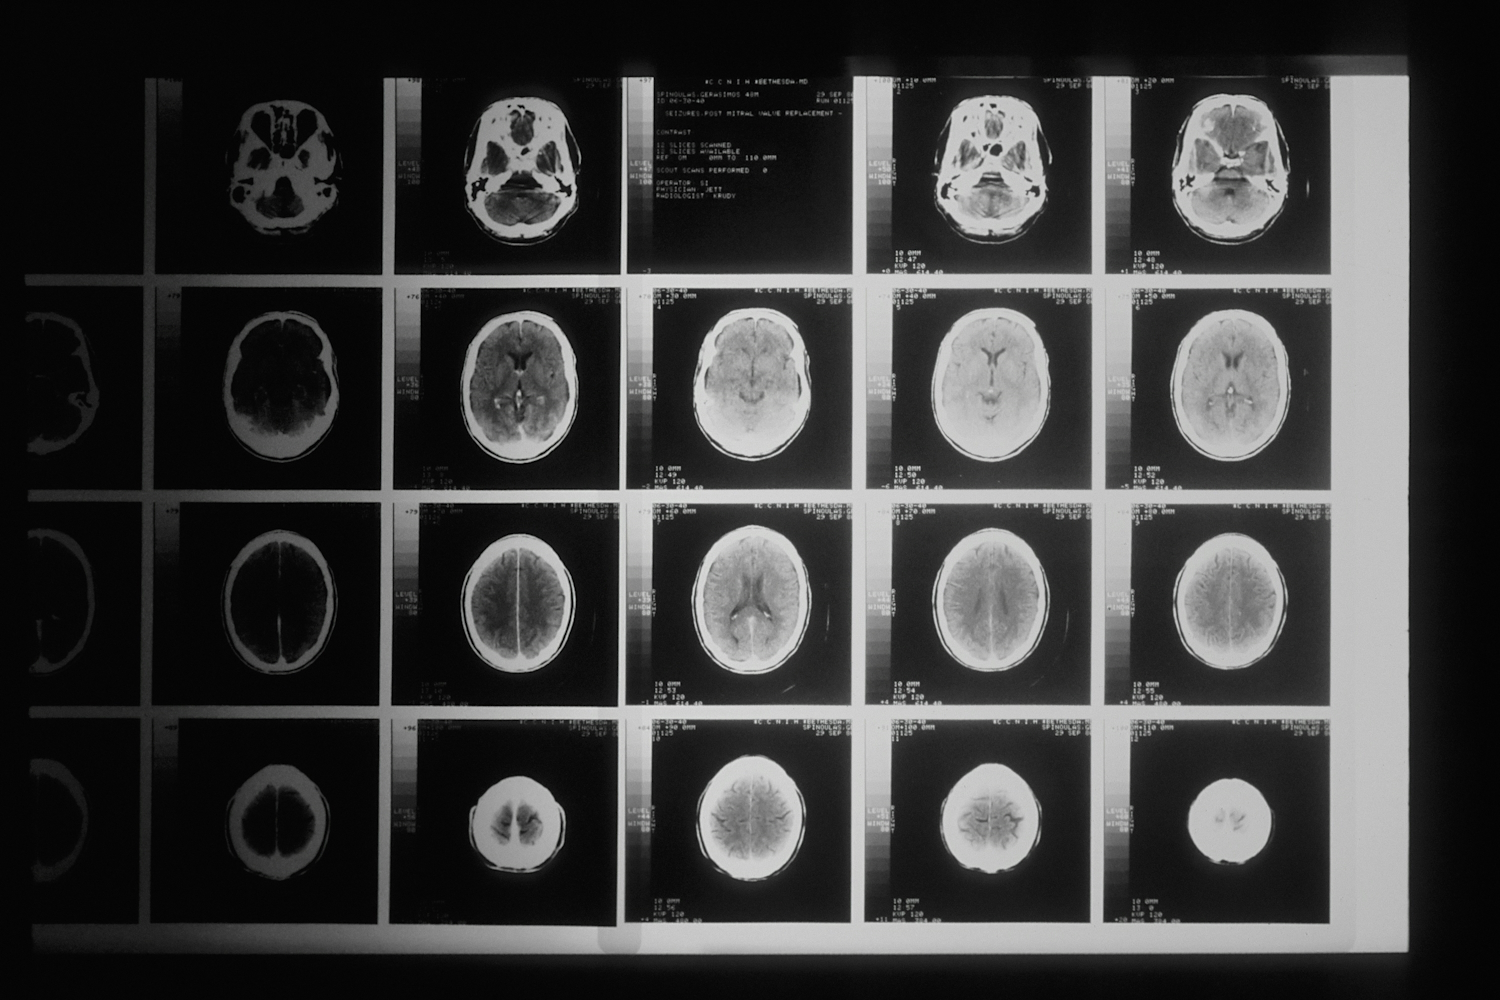

When you’re facing a brain cancer diagnosis, it’s hard to know where to start. India has quietly become one of the most reliable places in the world for advanced brain cancer treatment, not just because of cost, but because of the people and precision behind the care. Each year, more than 28,000 new brain tumor cases are diagnosed in the country, and while outcomes vary by tumor type, studies show that survival rates for glioblastoma in India, around 62% at one year and 30% at two years, are now on par with international standards. Whether you're seeking minimally invasive surgery, CyberKnife therapy, or a second opinion from a top neurosurgeon, the options here are both comprehensive and accessible. In this guide, we’ll break down what treatment actually looks like in India, which hospitals are leading the way, and how to connect with the right specialists.